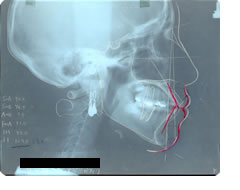

さて検査をして患者さんと相談です。頭部X線規格写真(セファログラム)をお見せしながら、小臼歯を抜歯して治療した場合の口唇の変化を予測してお話しします。

白の線が今の歯と唇です。歯を抜いて治療すると赤の直線の位置まで前歯が下がります。すると赤い線のように唇の形が変化します。より美しくなる方向です。

近年はコンピュータなどで口唇の形を予測するソフトがありますがそれらは平均値を使っているため、精度がよくありません。唇の形や閉じ方は人により千差万別です。経験のある歯科矯正専門医は個人にあわせて的確に治療後の予測をする事ができます。